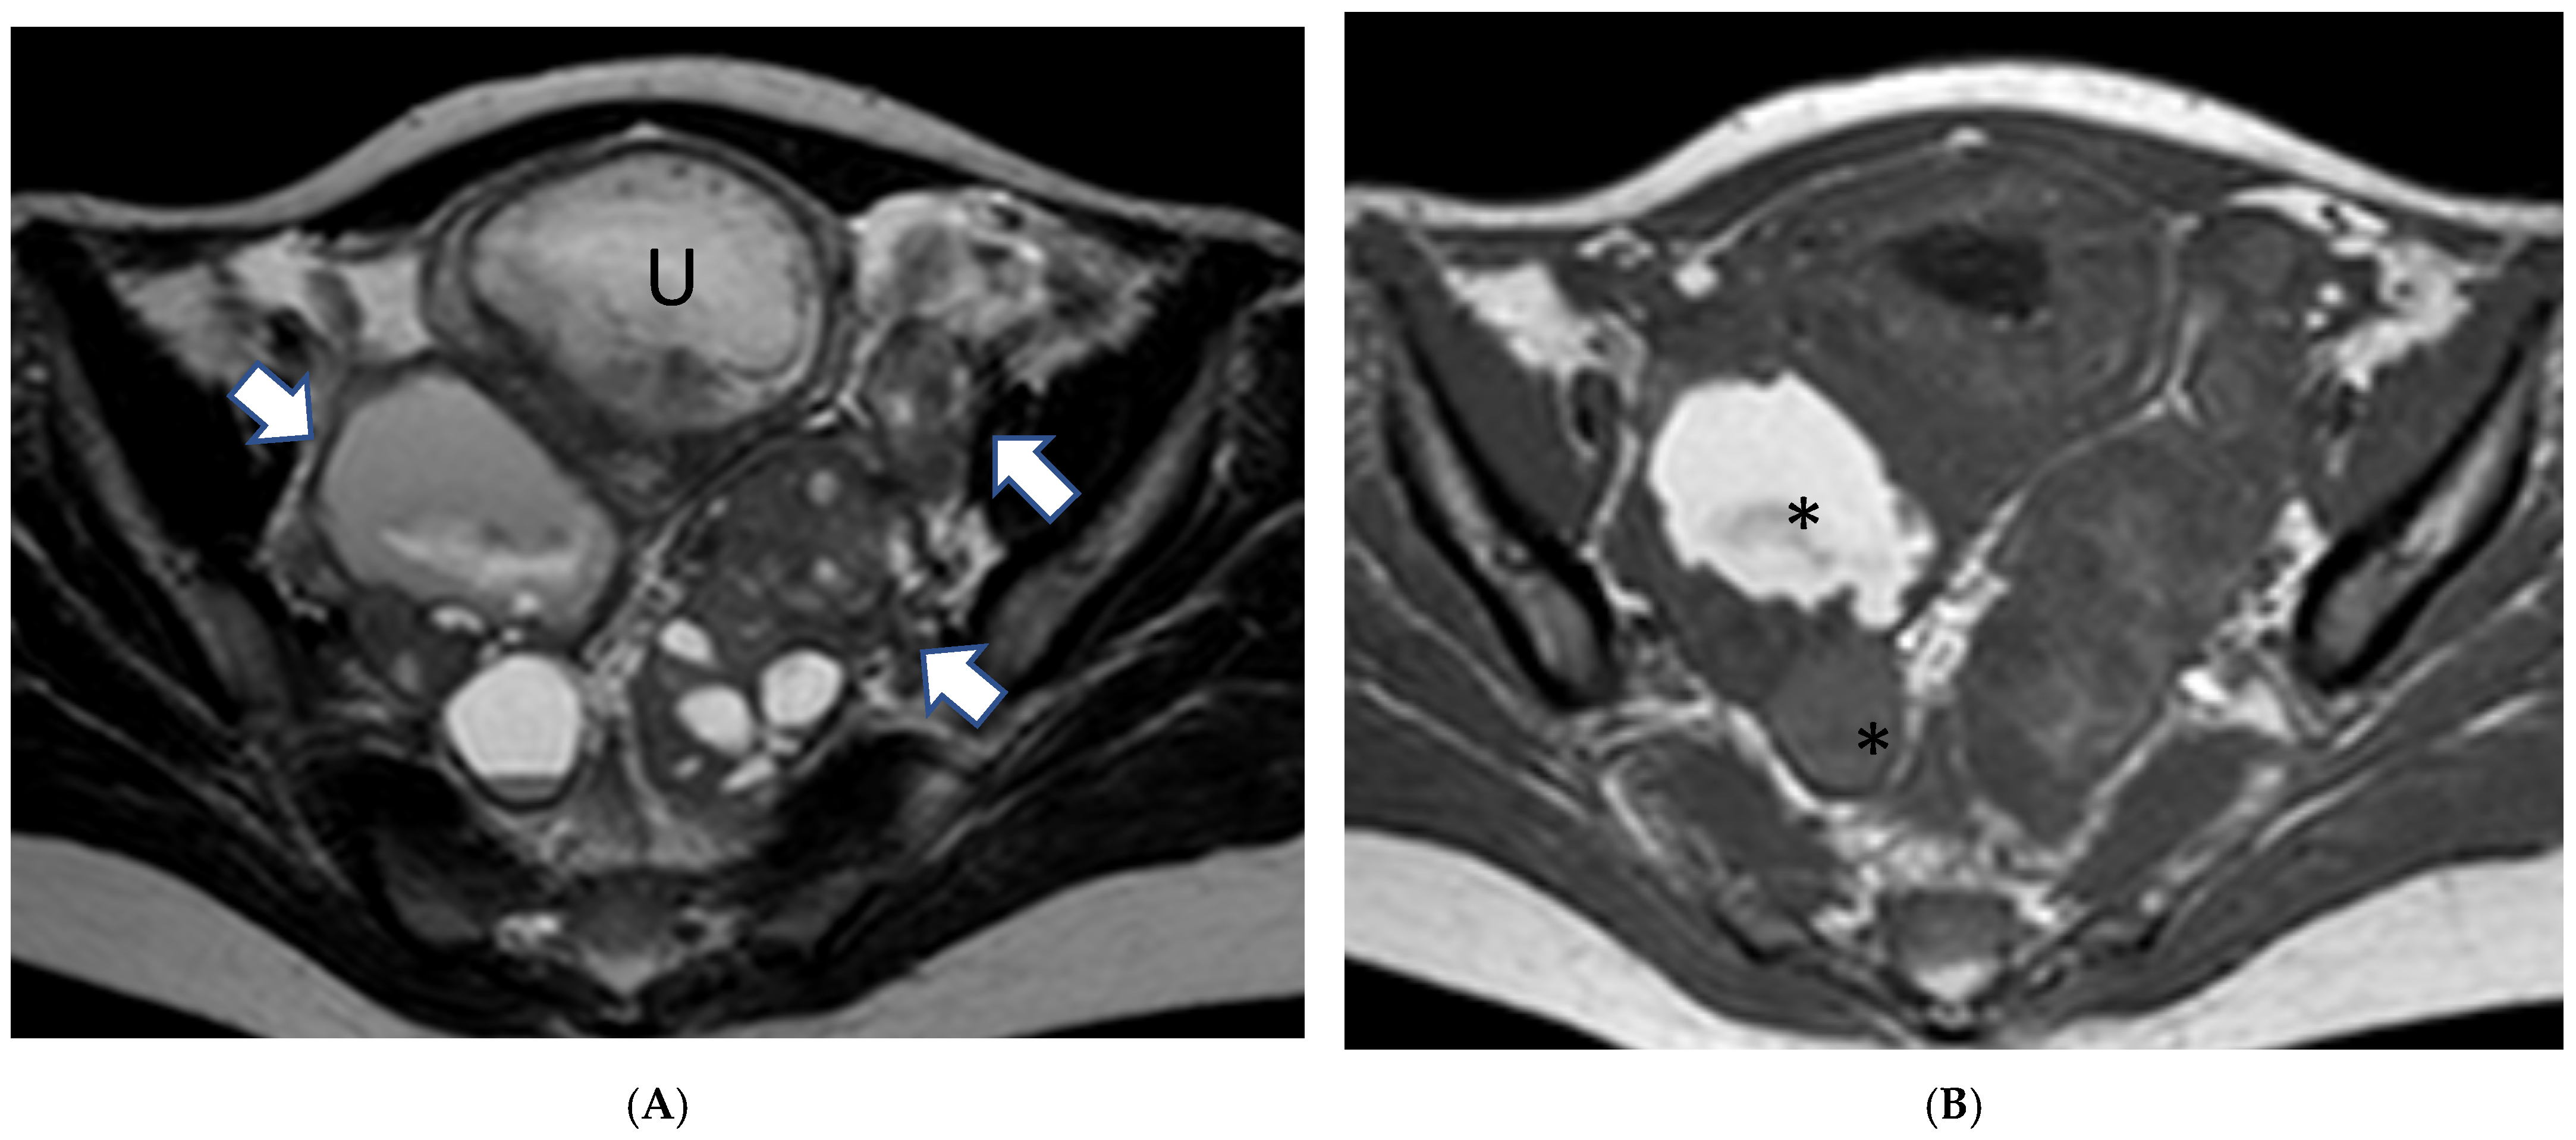

3.2.2. Imaging

3.2.3. Mimickers of Malignancy

- Panico, C.; Bottazzi, S.; Russo, L.; Avesani, G.; Celli, V.; D’erme, L.; Cipriani, A.; Mascilini, F.; Fagotti, A.; Scambia, G.; et al. Prediction of the Risk of Malignancy of Adnexal Masses during Pregnancy Comparing Subjective Assessment and Non-Contrast MRI Score (NCMS) in Radiologists with Different Expertise. Cancers 2023, 15, 5138. [Google Scholar] [CrossRef]

- Takeuchi, M.; Matsuzaki, K.; Nishitani, H. Magnetic resonance manifestations of decidualized endometriomas during pregnancy. J. Comput. Assist. Tomogr. 2008, 32, 353–355. [Google Scholar] [CrossRef] [PubMed]

- Morisawa, N.; Kido, A.; Kataoka, M.; Minamiguchi, S.; Konishi, I.; Togashi, K. Magnetic resonance imaging manifestations of decidualized endometriotic cysts: Comparative study with ovarian cancers associated with endometriotic cysts. J. Comput. Assist. Tomogr. 2014, 38, 879–884. [Google Scholar] [CrossRef] [PubMed]